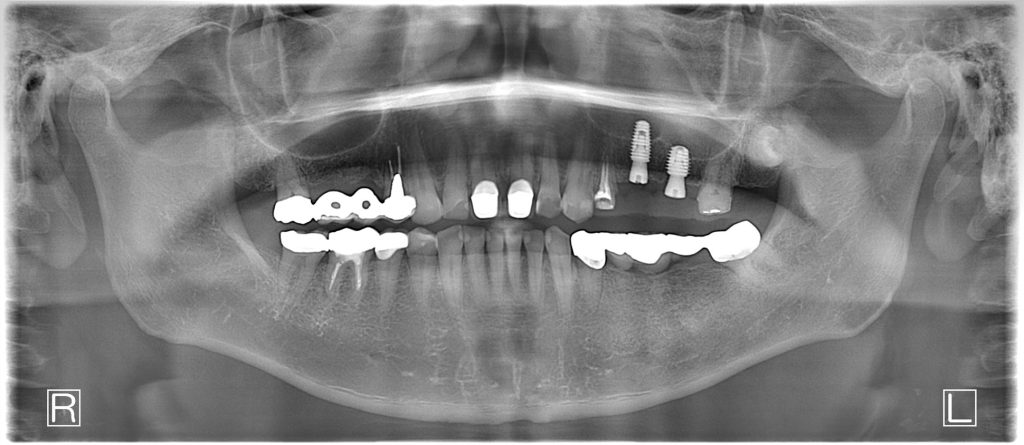

50代、男性、左上に違和感があることを主訴に来院され、インプラント治療を行いました。

| 診断結果 | 左上5番歯根破折 |

| 治療内容 | 抜歯即時インプラント |